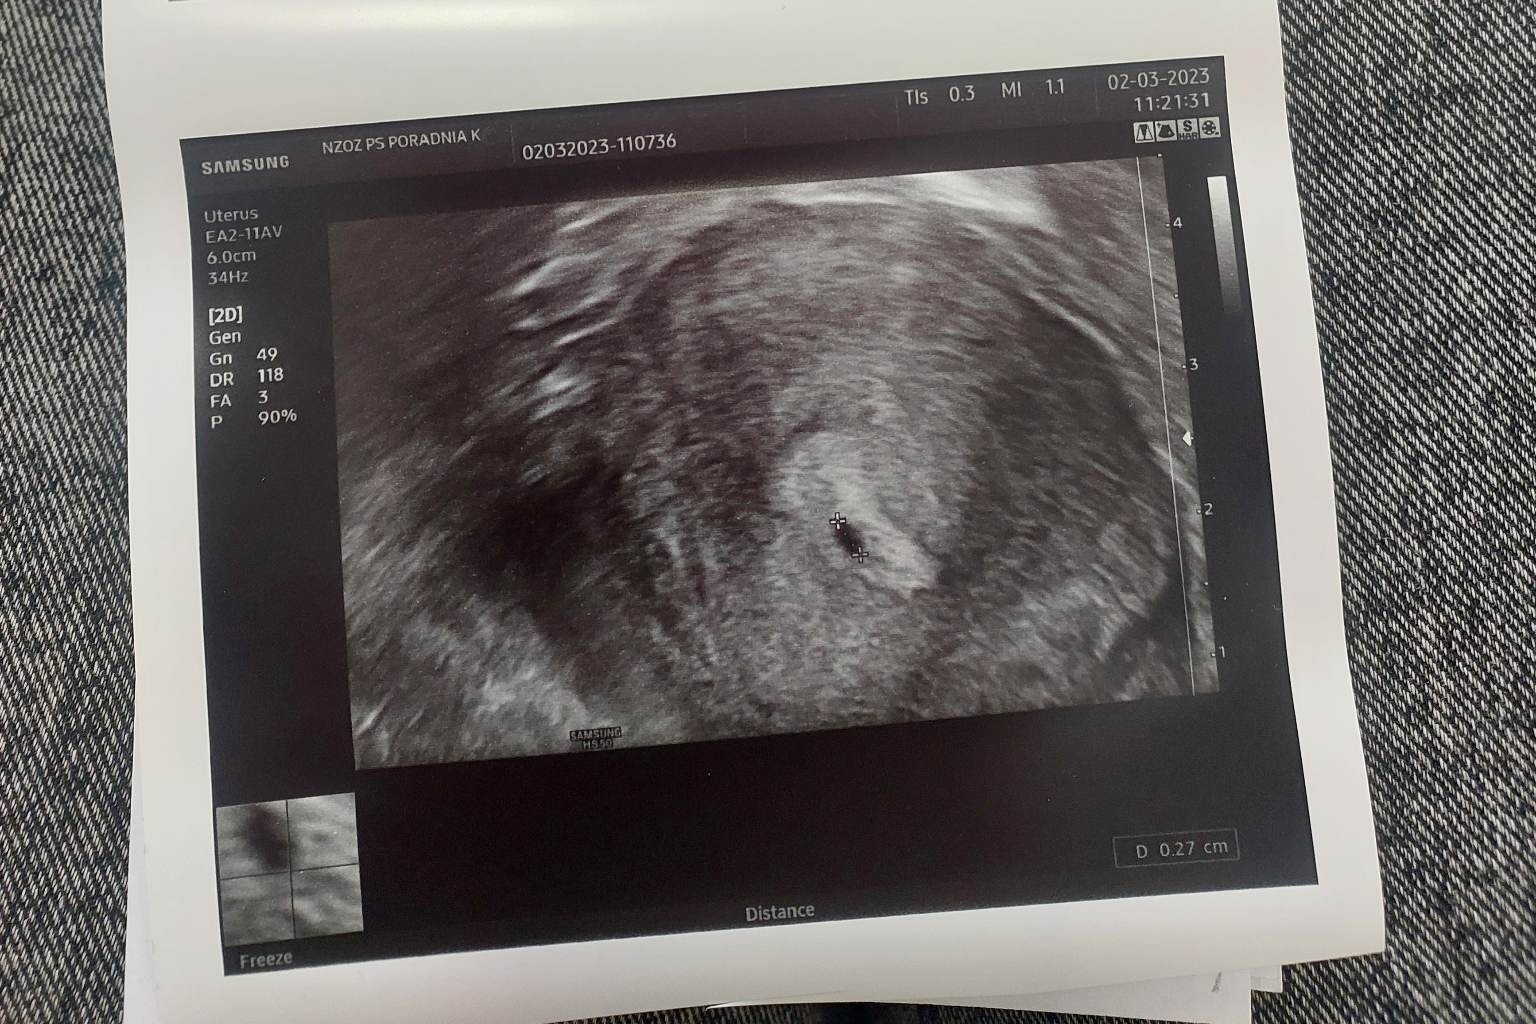

Witam. Byłam kilka dni temu u lekarza... stwierdził pęcherzyk 2 mm na USG, stwierdził,że to wskazuje na baaaardzo wczesna ciążę... nawet kilku dniowa. Zlecił badanie krwii beta. Na krwii wyszło w jednostce 1, gdzie ciąża jest od 6 ml... lekarz powiedział, że za 2 tyg sprawdzimy co się dzieje... Czy któraś mama tak miała i wyszło, że jednak jest to ciąża...

Tak, wyszło 1 ml... A pecherzyk jest 2 mm...

To przy takiej becie niemożliwe raczej, aby to byla ciąża. Ciążę na usg widać, gdy beta ma gdzies 1000